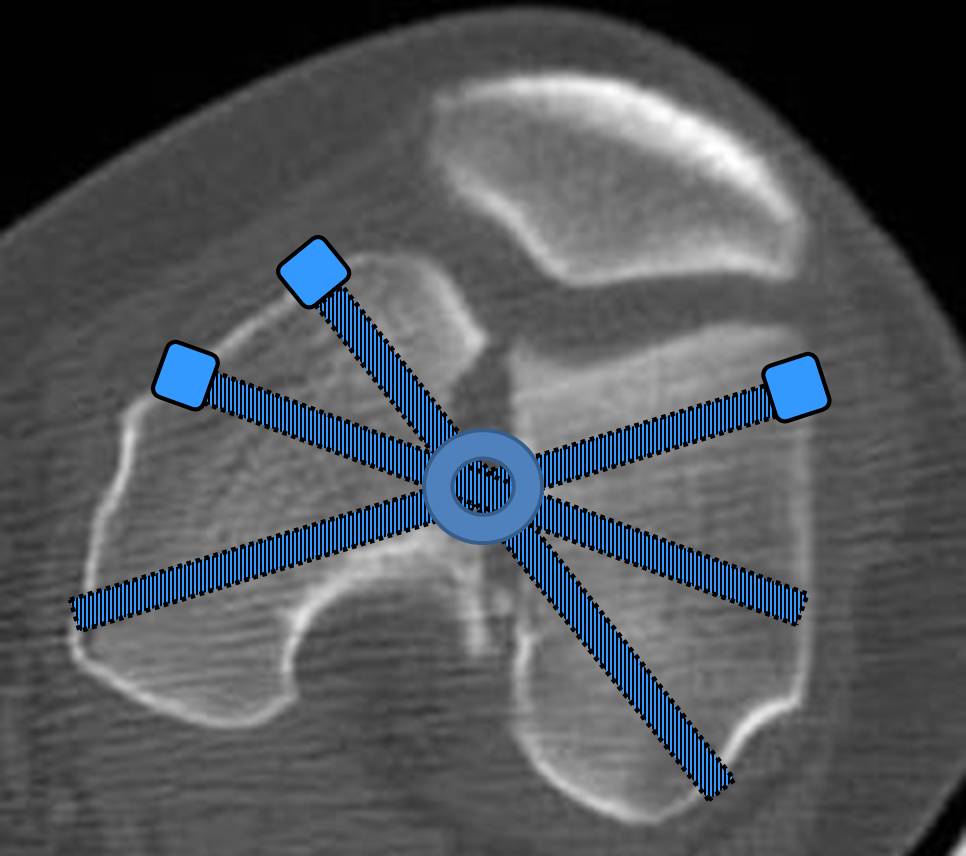

И уже лет шесть мы используем возможность ввести в дистальное овальное отверстие 3 винта, которые именно запираются в этом отверстии, не люфтят, а обеспечивают угловую стабильность - см картинку.

Получается и стабильно, и очень дистально, нижний край отверстия в 3 мм от дистального конца гвоздя.

Наш гвоздик, выпускаемый предприятием ЦИТО, тоже скорее из универсальных, хотя и с расширенными возможностями для дистальных переломов. Это овальное отверстие внизу задумывалось как динамическое для высоких переломов, очень дистально его разместили, чтобы не опасаться перелома гвоздя по этому отверстию. А возможность вот такого введения винтов, образующих "сборный клинок", обнаружилась года через 3 его применения.